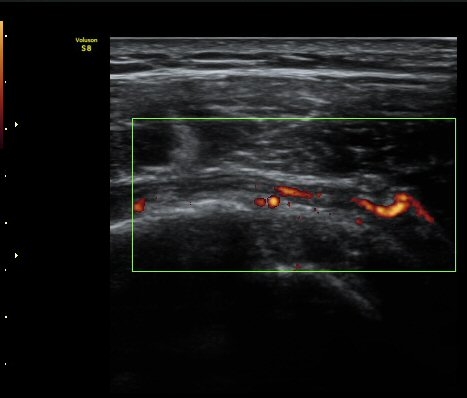

ÆÄ¿öµµÇ÷¯°Ë»ç¿¡¼­ ±Ø»ó°Ç°ú Á¡¾×³¶ÁÖÀ§¿¡¼­ ¼ö¾×Àú·ù°¡ °üÂûµÈ´Ù(±×¸² 6, 7).